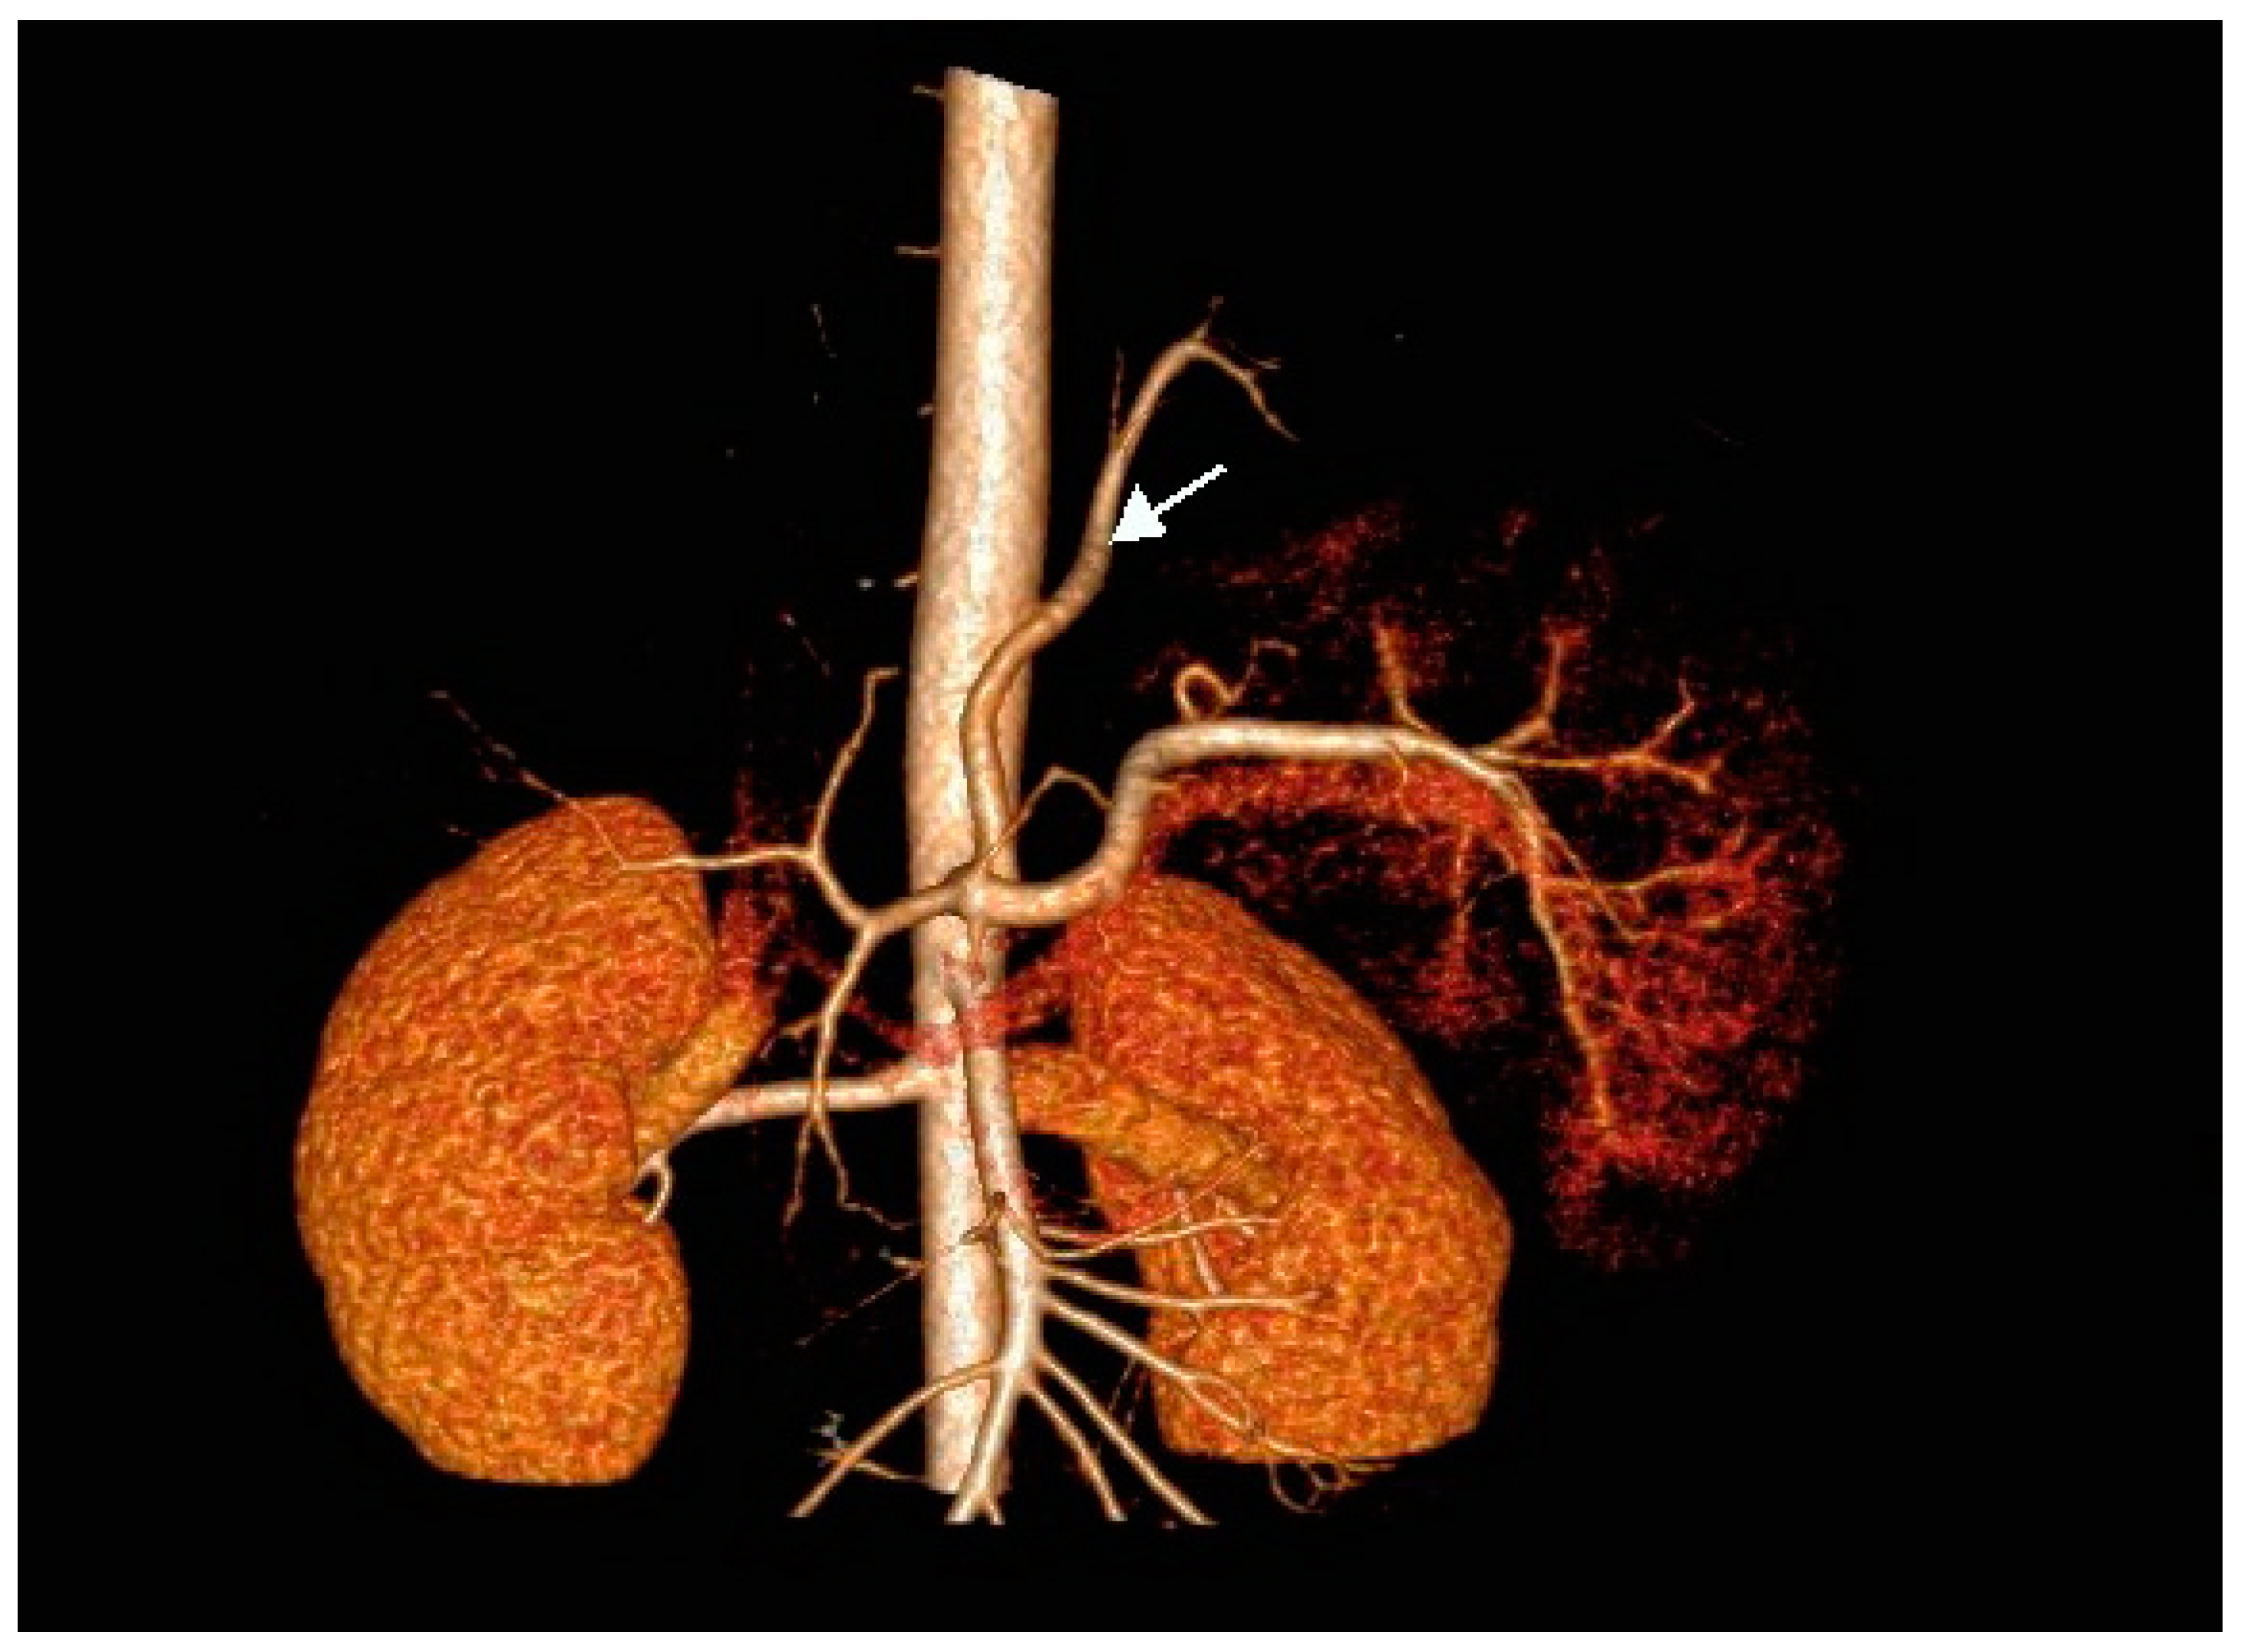

There was no communication of the affected lung parenchyma with bronchi of the left inferior lobe. We noted no further infiltrative changes in the remainder of the left and right lungs. Contrast-enhanced CT scanning with 3D reconstruction showed normal configuration of the thoraco-abdominal aorta, celiac trunk, and renal arteries. The celiac trunk originated from the abdominal aorta at the level of the intervertebral space Th12-L1. The systemic feeding artery (proximal diameter of 5 mm) originated from the celiac trunk. This artery supplied the pulmonary intralobar sequestration in the inferior lobe of the left lung (Figure 2a,b).

Figure 2. (a) Contrast-enhanced CT scan of the thoraco-abdominal aorta with 3D reconstruction of aorta, celiac trunk, and renal arteries. Note the feeding artery (indicated by arrow) with a diameter of 5 mm supplying the sequestration in the inferior lobe of the left lung (antero-posterior [AP] view). (b) Anomalous artery arising from the celiac trunk (artery indicated by arrow; lateral view).